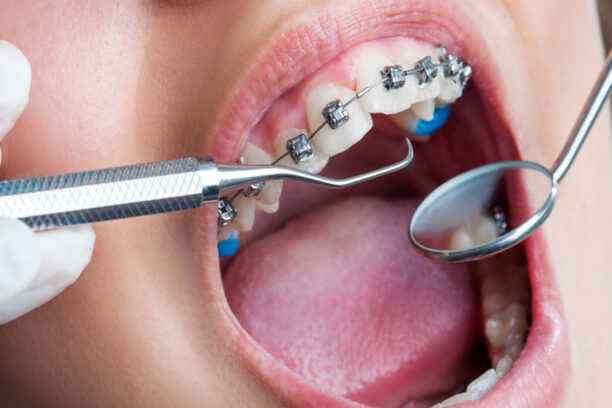

خطوات تركيب تقويم الأسنان

تمر عملية تركيب التقويم بسلسلة خطوات دقيقة ومدروسة لضمان نتائج مستقرة وآمنة، خصوصًا لدى البالغين. تشمل الخطوات الأساسية:

- فحص سريري شامل للأسنان واللثة والأنسجة الداعمة.

- تصوير إشعاعي رقمي متقدم لتقييم العظم ومفصل الفك.

- تحليل الإطباق وتحديد مناطق الضغط غير المتوازن.

- وضع خطة علاجية مخصصة تراعي العمر والحالة الصحية.

- اختيار نوع التقويم الأنسب من حيث الفعالية والمظهر.

- تنظيف الأسنان وتجهيز الأسطح قبل التركيب.

- تثبيت أجهزة التقويم بدقة ميكانيكية عالية.

- تحديد جدول زيارات منتظم للمتابعة والتعديل.